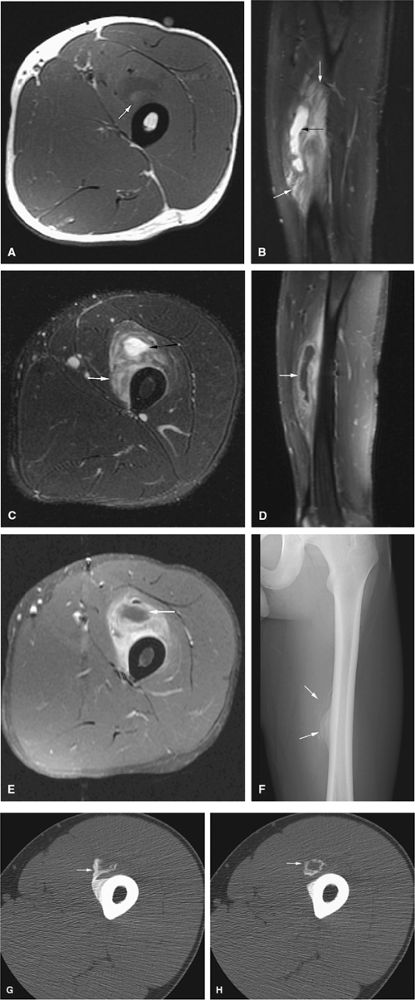

FIGURE 14-73 ● Parosteal osteosarcoma. Anterior coronal (A) and axial (B) T1-weighted images show a large lobulated mass of low signal intensity arising from the metadiaphyseal surface of the tibia (arrows). Tumor is hyperintense on sagittal (C) and axial (D) fat-suppressed T2-weighted fast spin-echo images. Tumor enhancement is noted on axial fat-suppressed T1-weighted image (E) following administration of intravenous gadolinium.